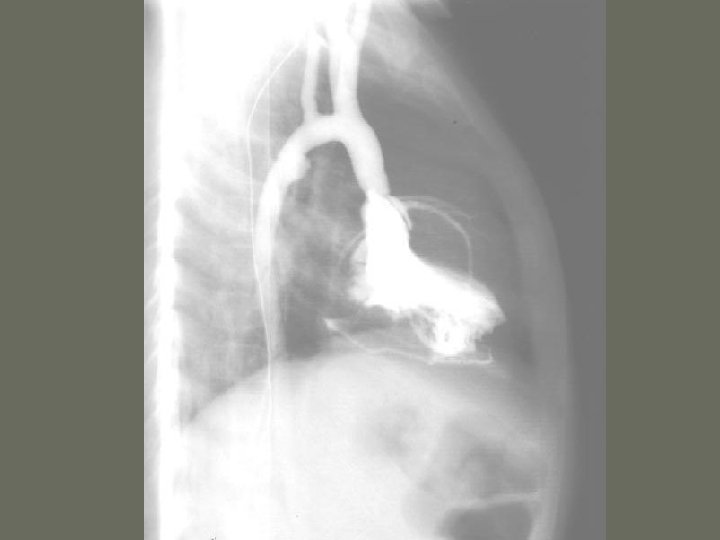

Cardiac Catheterization

Cardiac Catheterization • Angiocardiography 1. radiographic evaluation of the _______ of the heart and various valves 2. hemodynamic monitoring is the evaluation and recording of the function of the heart 3. include oxygen saturation, pressure tracings, and cardiac _______